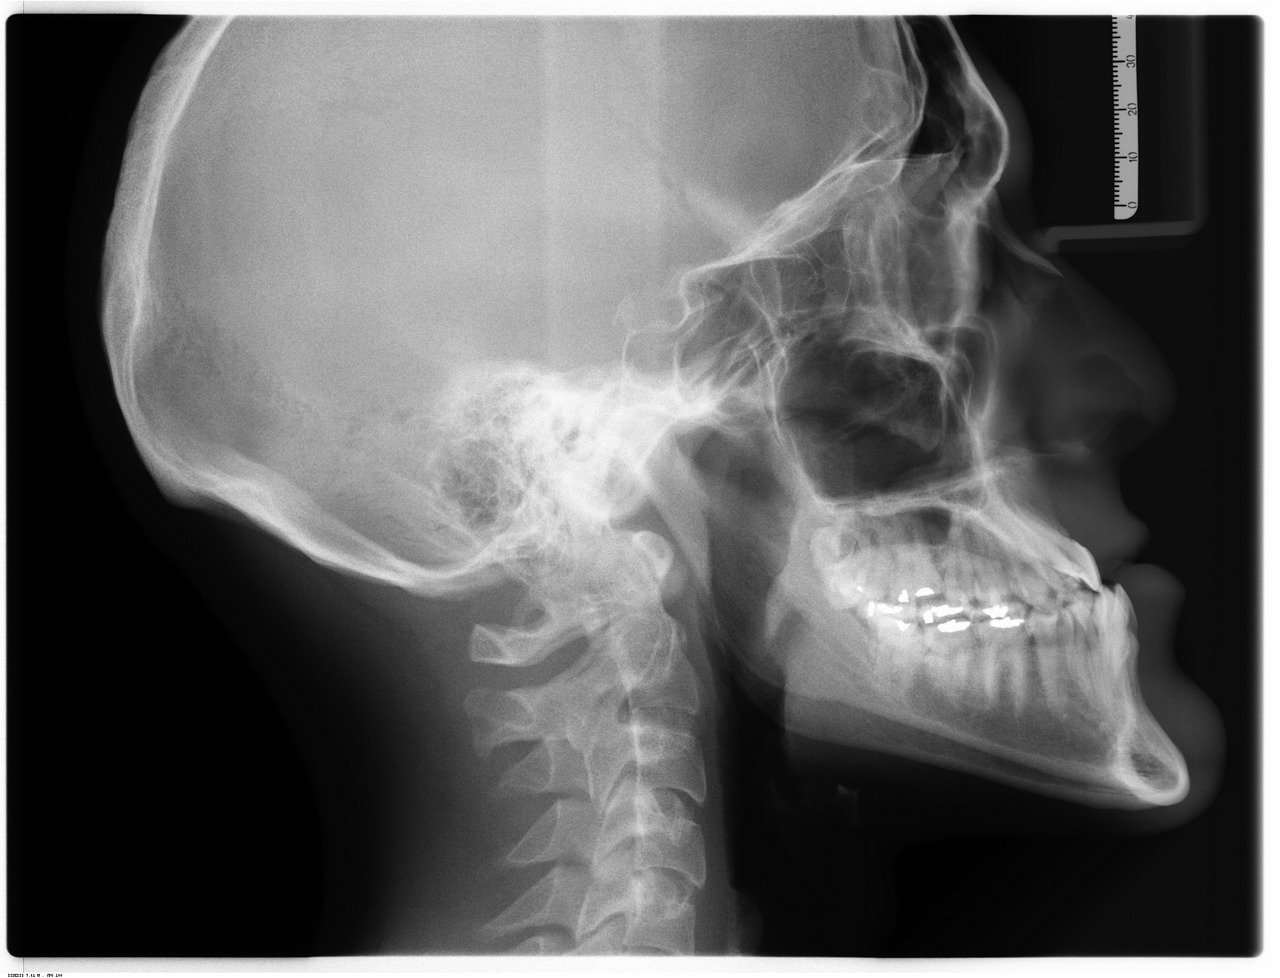

Quando falamos de radiologia médica, o primeiro pensamento é o raio-x, mas o campo abrange métodos que usam radiação ionizante (como tomografia computadorizada e mamografia) e outros que não usam, como a ressonância magnética e o ultrassom. Cada técnica tem seu papel: a TC é excelente pra ver detalhes ósseos e órgãos, enquanto a RM é imbatível pra tecidos moles, como cérebro e articulações.

Os exames de radiologia são variados e cada um atende a uma necessidade específica de diagnóstico. A radiografia convencional, popularmente conhecida como raio-X, é frequentemente o primeiro passo para avaliar fraturas ósseas ou condições pulmonares. A tomografia computadorizada (TC) oferece cortes transversais detalhados, ideais para investigar tumores, hemorragias e lesões complexas.